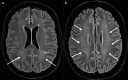

Medical imaging methods are assuming a greater role in the workup of patients with COVID-19, mainly in relation to the primary manifestation of pulmonary disease and the tissue distribution of the angiotensin-converting-enzyme 2 (ACE 2) receptor. However, the field is so new that no consensus view has emerged guiding clinical decisions to employ imaging procedures such as radiography, computer tomography (CT), positron emission tomography (PET), and magnetic resonance imaging, and in what measure the risk of exposure of staff to possible infection could be justified by the knowledge gained. The insensitivity of current RT-PCR methods for positive diagnosis is part of the rationale for resorting to imaging procedures. While CT is more sensitive than genetic testing in hospitalized patients, positive findings of ground glass opacities depend on the disease stage. There is sparse reporting on PET/CT with [18F]-FDG in COVID-19, but available results are congruent with the earlier literature on viral pneumonias. There is a high incidence of cerebral findings in COVID-19, and likewise evidence of gastrointestinal involvement. Artificial intelligence, notably machine learning is emerging as an effective method for diagnostic image analysis, with performance in the discriminative diagnosis of diagnosis of COVID-19 pneumonia comparable to that of human practitioners.